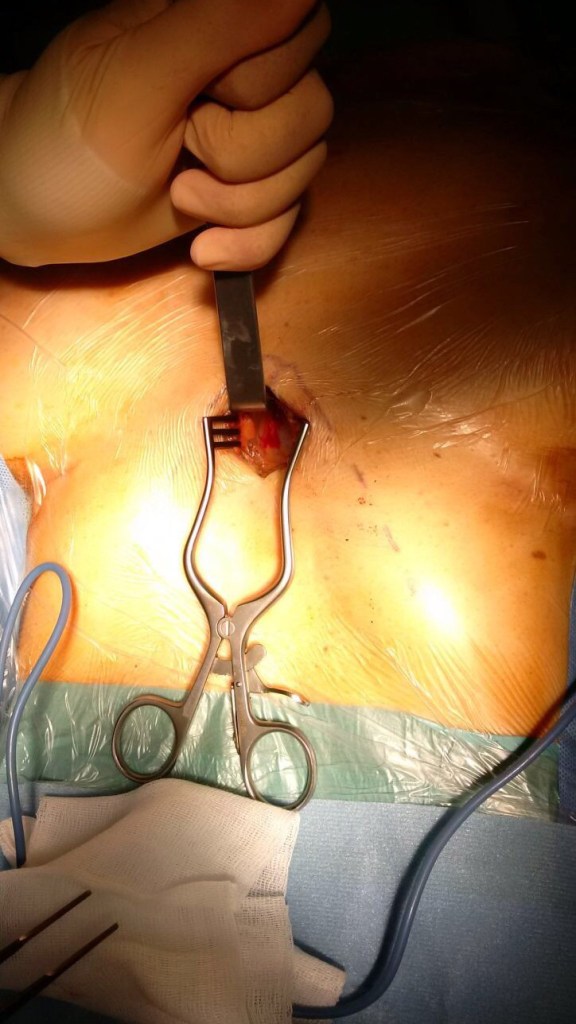

A 3.5-cm longitudinal muscle sparring incision was made below the xiphoid process between through the linea alba.

the incision

The xiphoid process was exposed,  the inferior part of the sternum was lifted up with a retractor and a blunt dissection was carried out in order to find the pericardial plane.

A SILS port (Covidien, Mansfield, MA) was then inserted into the port, and CO2 was insufflated at a maximal pressure of 8 mm Hg. The CO2 insufflation within the mediastinum generates a very useful  amount of extra working space within the anterior-superior mediastinum allowing an easier dissection and a better visualization of the mediastinal structures especially toward the cranial part of the mediastinum cephalad to the left innominate vein including the upper poles of the thymus.